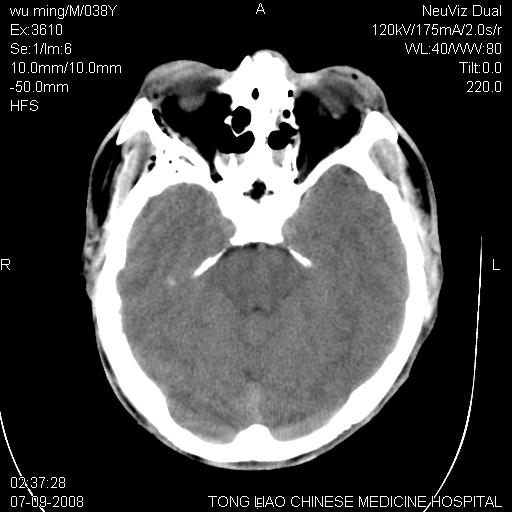

颅底多发骨折。

颅底多发骨折.

1)颅底骨及颌面骨多发性骨折。2)副鼻窦及双侧鼻腔积血。

颅底骨折,窦腔内积血。考虑死亡原因为脑水肿压迫脑干或因大量失血死亡。

前颅窝颅底骨折,死的原因应该从头部来看不用说就是重度颅脑损伤。